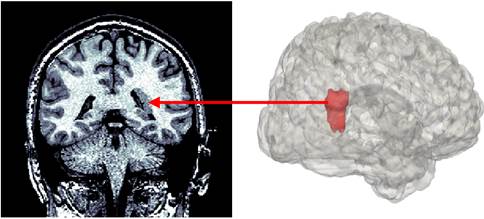

在人类大脑的发育过程中,神经元在新生期进行迁移从而抵达它们正确的位置。该过程是脑功能发育的关键之一。神经元迁移过程异常可能会导致神经元出现在异常位置,如室周结节异位(Periventricular nodular heterotopia, PVNH),即在侧脑室壁周围形成灰质结节(图1)。那么,这些迁移失败的神经元是否与新皮层存在功能连接?这是一个有趣但悬而未解的问题。

图1 灰质异位示例